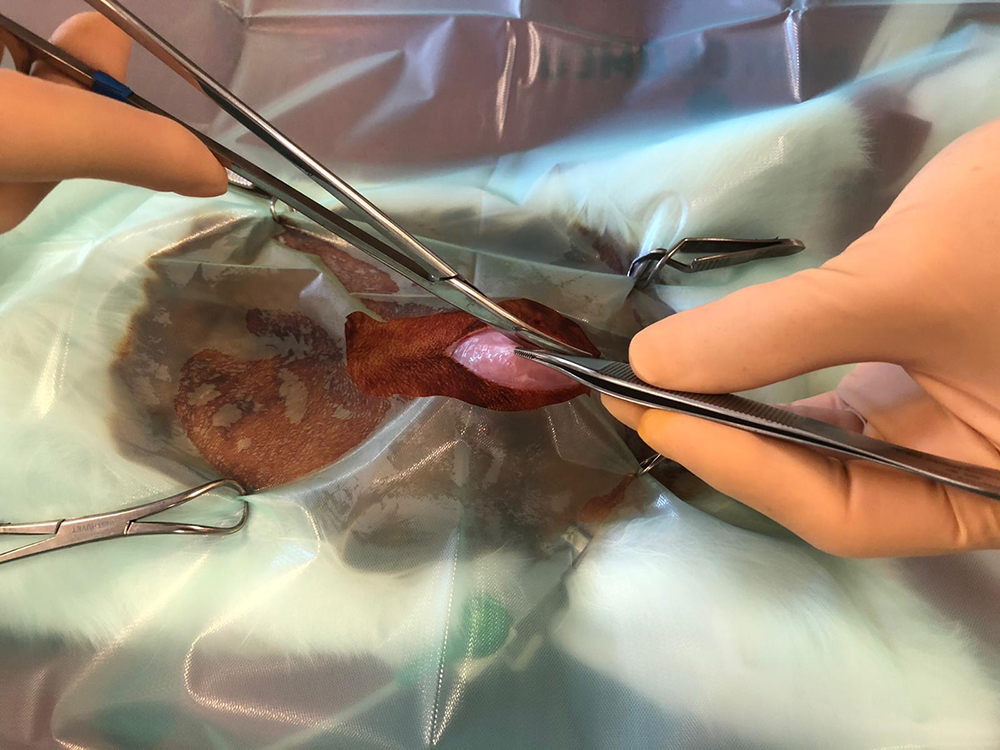

Na het afbinden van de bloedvaten worden de eierstokken en de baarmoeder verwijderd. Hierbij wordt goed opgelet dat ook daadwerkelijk de hele eierstok verwijderd wordt, wat soms lastig te zien is door het vet eromheen.